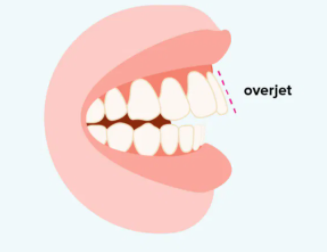

En la relació sagital a nivell incisal té un overjet amb augment del ressalt, ja que mesura més de 3 mm el ressalt, i l'overbite és a dir sobremossegada és negativa, ja que hi ha una mossegada oberta, anterior. I en la relació transversal molar té una mossegada normal.

OVERJET